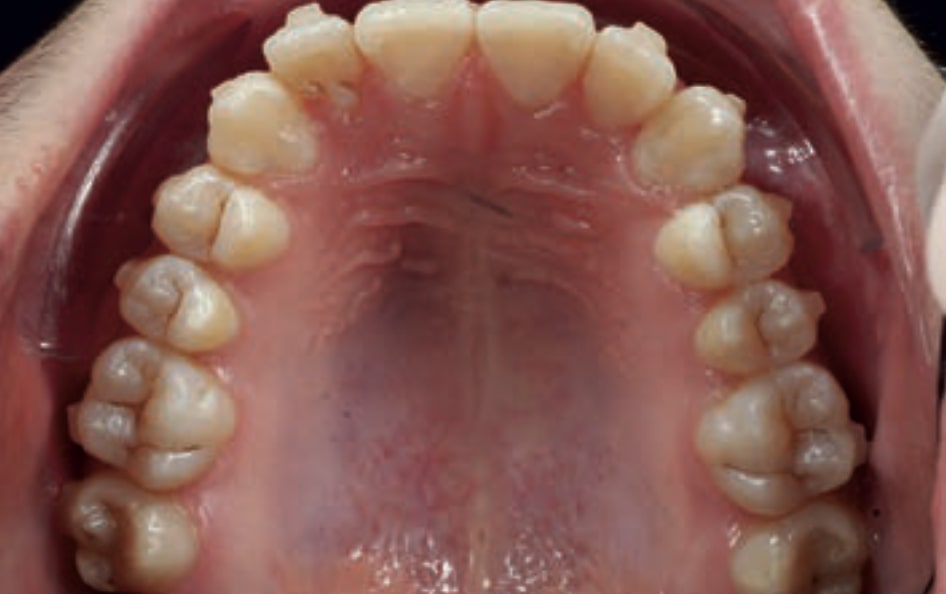

Chief complaint: The patient, a 19-year-old woman, was evaluated to undergo orthodontic treatment using the Angel Aligner Pro system. She presents with a skeletal Class III, mesofacial, with a dental Class III malocclusion and a 2 mm deviation of the lower midline to the left. Teeth 33 and 43 are out of the arch and cortical bone, with a crossbite issue on tooth 33. Fortunately, no functional issues affecting swallowing or breathing have been detected. The patient’s motivation for starting treatment was a general review of her dental and aesthetic health. The soft tissue analysis reveals mandibular protrusion that influences her facial profile. This diagnosis highlights the need for a comprehensive approach to address dental and skeletal misalignments, improving both the patient’s functionality and facial aesthetics.

- Dental Class III, 2 mm deviation of the lower midline to the left. 33 and 43 out of the arch and the cortical bone.

- Crossbite of 33.